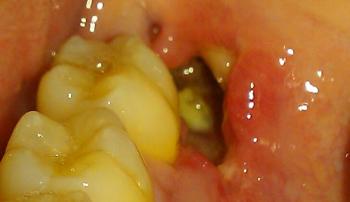

We see this too often in our clinic. Children from high-stress or separated families sometimes present with more cavities and gingivitis. It’s not just about sugar; it’s about sadness. When the structure of "goodnight, brush your teeth" crumbles, the consequences are more than just dental.